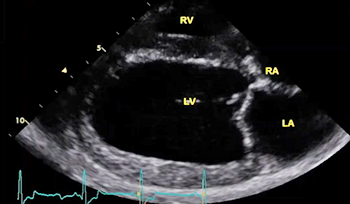

The echocardiograph examination shows the dimensions of the heart chambers, wall thickness and movement, valve movement and lesions, fractional shortening, among other characteristics. The echo screen shows the amount of wall contraction, which enables the operator to determine contractility, preload*, and afterload*. These factors are used to calculate "fractional shortening" (FS%) which is used as an indication of ventricular performance and of myocardial contractility.

* Preload is the blood filling the left ventricle, thereby stretching the heart muscle cells before contraction. Afterload is the blood contained in the left ventricle against which the heart contracts to eject that blood into the arteries.

(In the image at right, the red spurt of blood is shooting upward and backward, from the left ventricle, through the not-fully-closed mitral valve, back into the left atrium.)